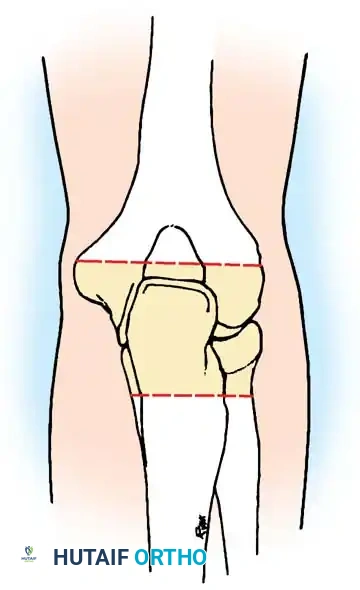

Surgical Management: Knee Arthrodesis

For advanced destruction, knee arthrodesis provides a stable, painless limb.

1. Approach: A standard anterior midline incision with a medial parapatellar arthrotomy.

2. Debridement: Radical synovectomy and excision of the menisci, cruciate ligaments, and infected bone.

3. Bone Cuts: Flat cuts are made on the distal femur and proximal tibia to ensure maximum cancellous bone contact. The knee is positioned in 5 to 10 degrees of flexion and neutral mechanical alignment.

4. Fixation: An intramedullary nail or dual-plate construct is utilized for rigid biomechanical stability.